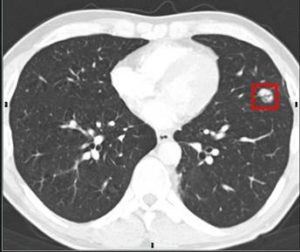

Lung Cancer Screening X Ray

Experience the clarity of Lung Cancer Screening X Ray with our curated collection of comprehensive galleries of images. featuring understated examples of photography, images, and pictures. designed to emphasize clarity and focus. Discover high-resolution Lung Cancer Screening X Ray images optimized for various applications. Suitable for various applications including web design, social media, personal projects, and digital content creation All Lung Cancer Screening X Ray images are available in high resolution with professional-grade quality, optimized for both digital and print applications, and include comprehensive metadata for easy organization and usage. Our Lung Cancer Screening X Ray gallery offers diverse visual resources to bring your ideas to life. Comprehensive tagging systems facilitate quick discovery of relevant Lung Cancer Screening X Ray content. Multiple resolution options ensure optimal performance across different platforms and applications. Time-saving browsing features help users locate ideal Lung Cancer Screening X Ray images quickly. The Lung Cancer Screening X Ray archive serves professionals, educators, and creatives across diverse industries. Instant download capabilities enable immediate access to chosen Lung Cancer Screening X Ray images. Whether for commercial projects or personal use, our Lung Cancer Screening X Ray collection delivers consistent excellence. Professional licensing options accommodate both commercial and educational usage requirements.